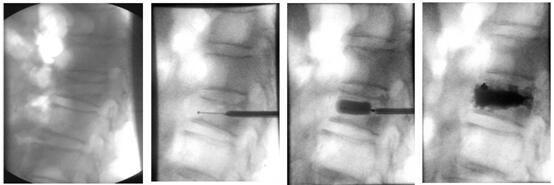

下面带大家了解椎体成形术是怎样做的!

患者俯卧位在手术床上,透视标记骨折椎体;

穿刺点局部麻醉,根据定位将穿刺锥穿入骨折椎体;

透视确定穿刺锥进入骨折椎体后,建立工作通道;

等待15分钟骨水泥凝固硬化,手术结束。病人即刻疼痛消失,术后第一天可以下床活动。